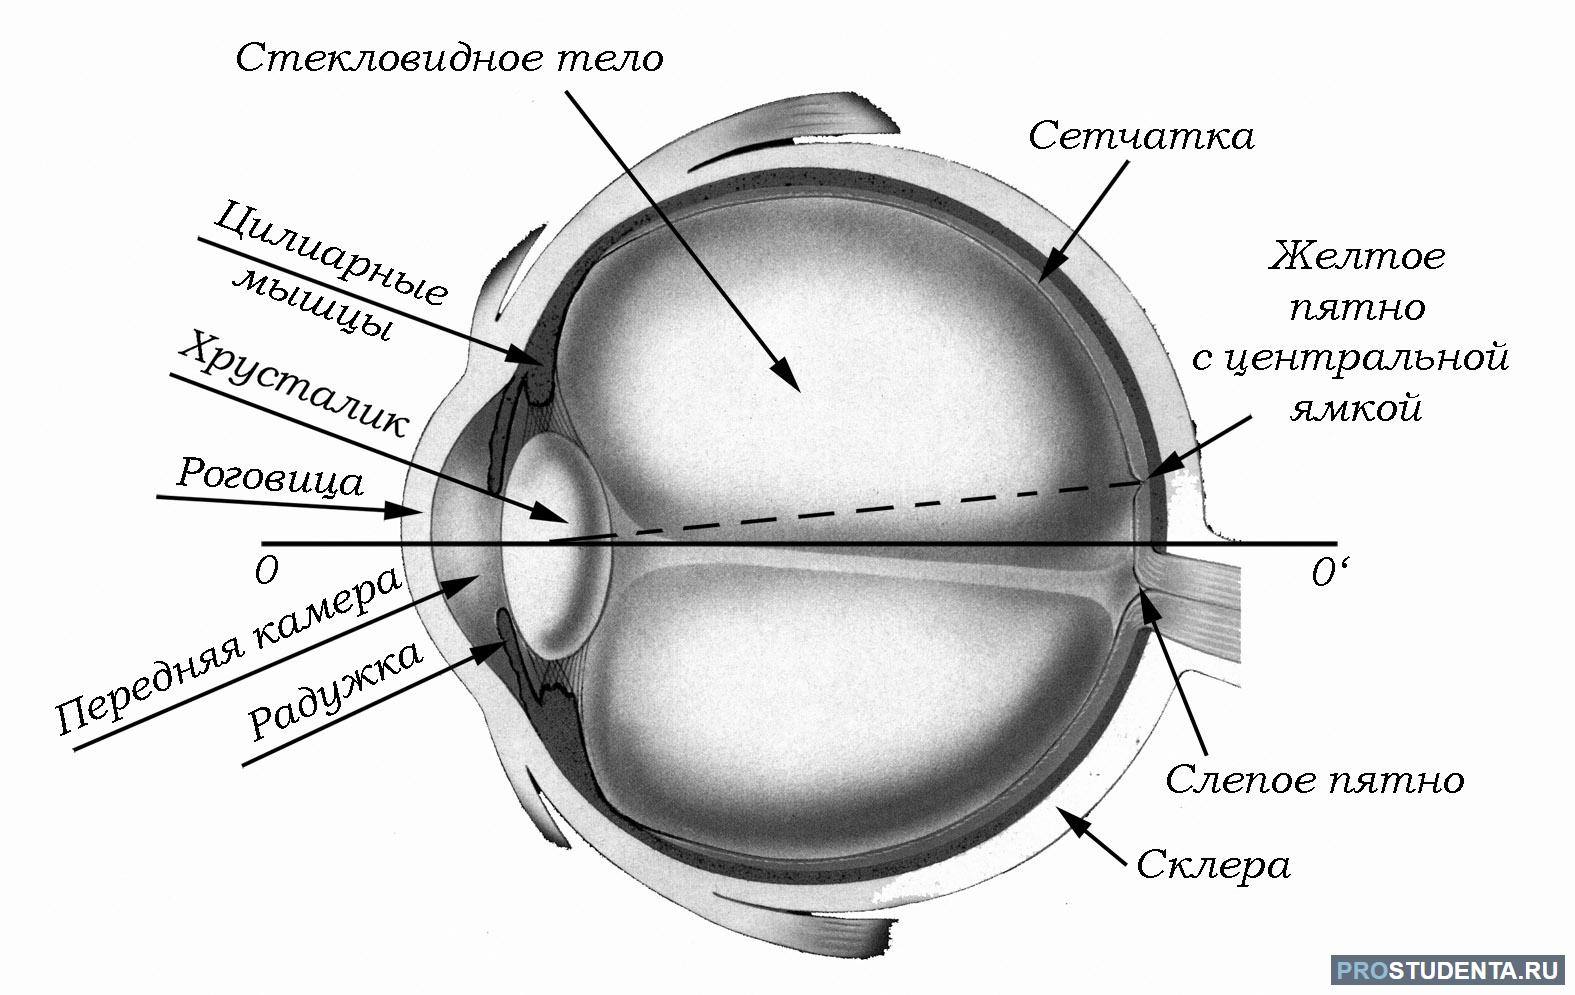

КТ-графики и изображение строения глаза